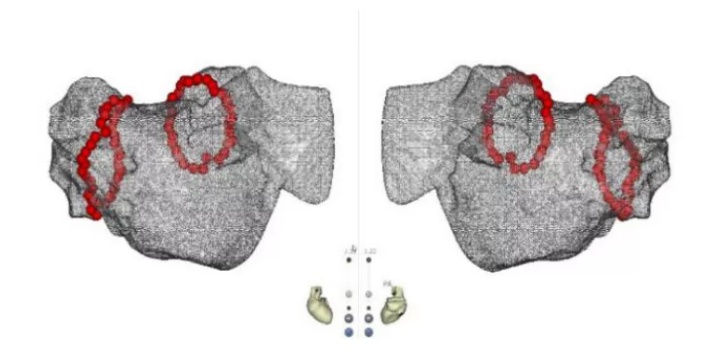

图1:术中心腔内超声指导下零射线电隔离两侧肺静脉

一个月后,肖方毅医师在心腔内超声和三维电解剖标测系统指导下为蔡老伯成功实行房颤射频消融联合左心耳封堵术。这是目前最新的技术,整个消融过程因为有心腔内超声的指引,无需任何射线,直视下精准构建左房模型,精准消融(图1)。消融后肖方毅医师用自己创立的“FLAVOR”术式,在腔内超声指导下顺利植入左心耳封堵器(图2,图3),避免了以往术中需要做经食道心超检查的痛苦。